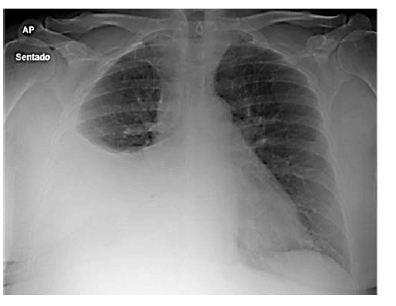

Paciente do sexo feminino, de 27 anos de idade, casada, técnica de enfermagem de uma unidade de pronto atendimento (UPA), comparece ao setor de emergência com queixa de dispneia havia 1 semana e indisposição, havia 1 mês. Era tabagista ativa e não fazia uso de medicações regularmente. Na história ginecológica da paciente, não havia particularidades, a anticoncepção era realizada com preservativo masculino. Ao exame físico, apresentou-se em bom estado geral, hidratada e com sinais vitais estáveis. ausculta pulmonar, o murmúrio estava abolido no terço inferior do hemitórax direito. Nos exames complementares, o hemograma estava normal, as sorologias negativas. A imagem a seguir mostra o Raio X de tórax da paciente.